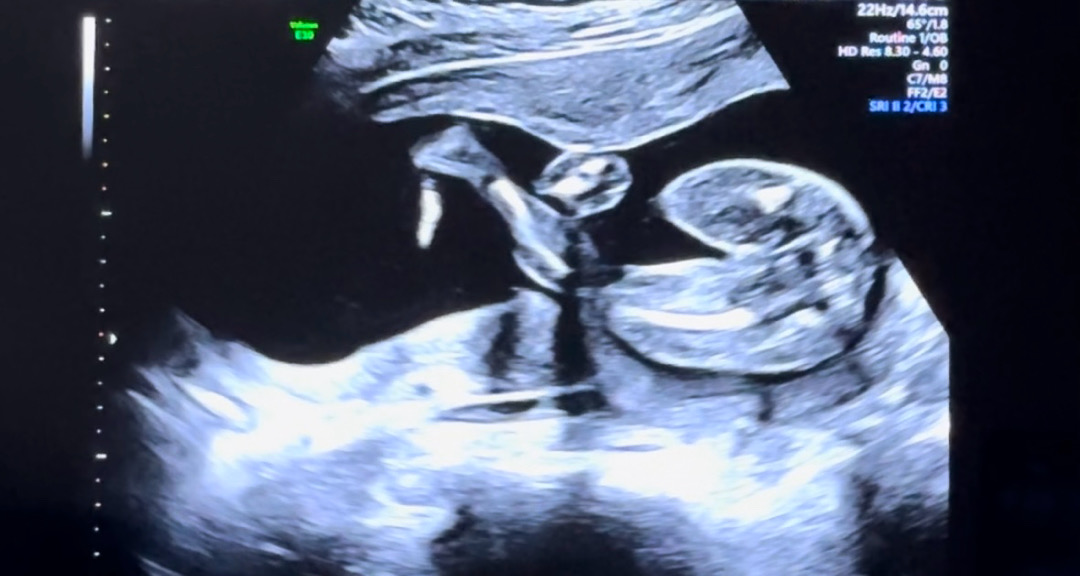

19주차인데 성별 보이시나요 ㅠㅠ

촘파쌤께선 다리를 오므린 상태라 잘 안보인다는데 저정도 각도면 🌶️없는거 아닌가요??? 대학병원이라 늦게 말해준다길래 궁금해 죽어요ㅠ 다리 오므리면 🌶️저렇게 안 보이나용??? 아들일수도 있을까용? 넘 궁금해요

여자아이에요!!!!!!!! 남자아이는 그정도 주수면 봐라!!! 이게 내 성별이다!!! 하고 보여주거든욬ㅋㅋㅋㅋ

그쵸!!? 이정도 주수땐 왠만하면 🌶️보일텐데 ㅋㅋㅋㅋ 감사합니당😎